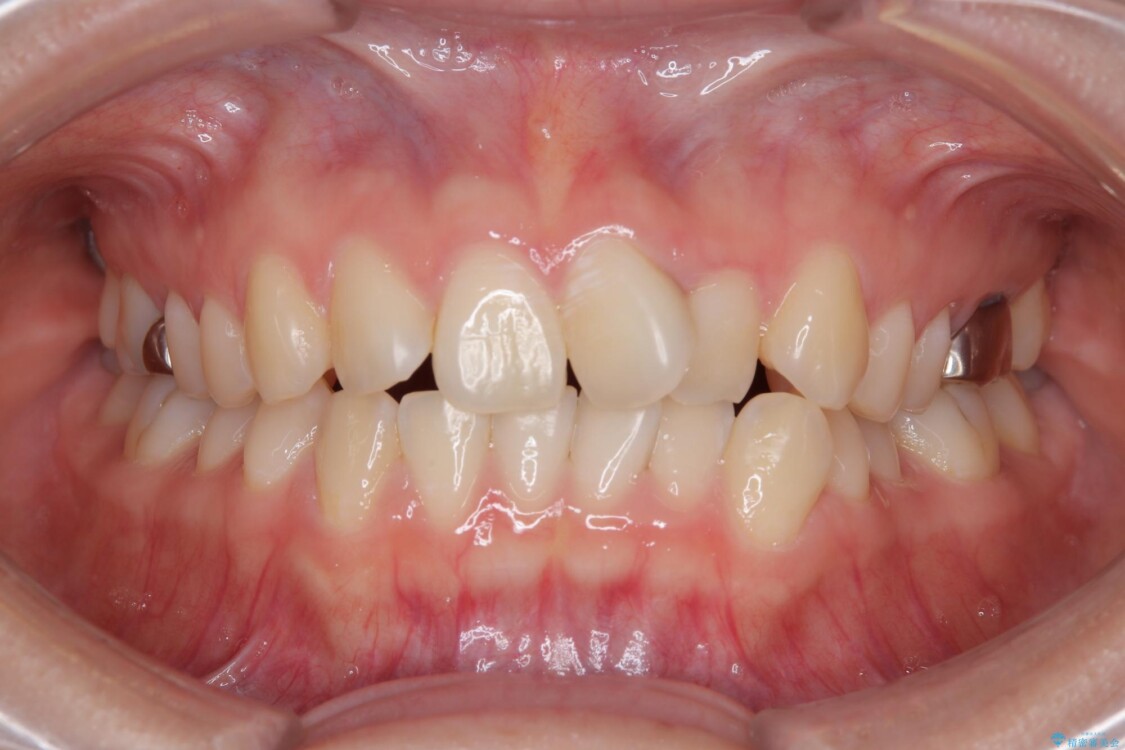

矯正治療期間はわずか10か月と、比較的短期間で終了しました。

前歯のデコボコがなくなり、見た目の印象が大きく変わっただけでなく、歯磨きがしやすくなり、むし歯や歯周病のリスクが大きく減少しました。

治療後

• 前歯のねじれ・ガタガタを10か月で改善!20代女性の矯正治療|クリアブラケットでむし歯になりにくい歯並びへ改善 治療後画像